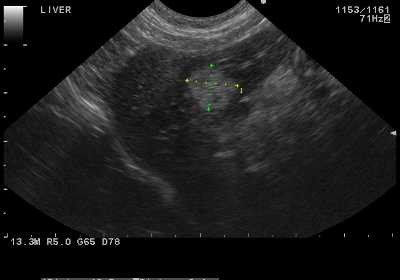

Step 06. エコー(超音波検査)

レントゲンと同様に、『腫瘍を探す』ための検査ですが、エコーは内臓の内部の腫瘍を探します。

肝細胞癌

肝臓内にわずか1cm弱のしこりがみつかりました。細い針で細胞を採取し細胞診でしこりの正体を突き止めます。